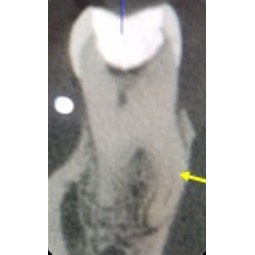

Three-dimensional imaging using CBCT is also very useful in identifying an additional root and treatment planning. It provides a ‘roadmap’ for endodontic treatment and highlights any curvatures present (Figure 5).

In a radix entomolaris, the main distal root (DB) may still have two canals (DB1 & DB2) (Figure 5). The DB2 is more difficult to locate and can be hidden in the isthmus between DB1 and DL. It is often in close proximity to DB1.

Use fine ultrasonics to conservatively open the isthmus to search for this canal (Figure 7).